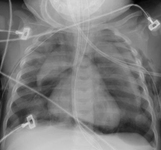

Hérnia diafragmática congênita

Do acervo de Ponthenkandath Sasidharan, MD; usado com permissão